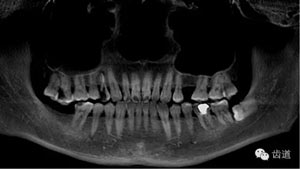

鄭玉琪:CBCT導(dǎo)航下尋找右上第一前磨牙三根管疑難病案一例

本病例為右上第一前磨牙三根管疑難病例,首診及二診由重慶醫(yī)科大學(xué)附屬口腔醫(yī)院牙體牙髓科下級(jí)醫(yī)生處理,因根管遺漏未能處理轉(zhuǎn)診上級(jí)醫(yī)生鄭玉琪老師進(jìn)行顯微根管治療。本病例是不可多得的如何避免遺漏根管及如何治療遺漏根管的帶教根管治療病例之一。

好的開(kāi)始就是成功的一半。通過(guò)CBCT了解根管的位置,形態(tài),方向。

檢查顯示:近頰及腭根充填恰填,遠(yuǎn)頰根管內(nèi)有少許充填物影像。根尖明顯低密度影像。

上頜第一前磨牙:87%為雙根管,其次為單根管,另有2.4%為三根管, 側(cè)支根管發(fā)生率49.5%;